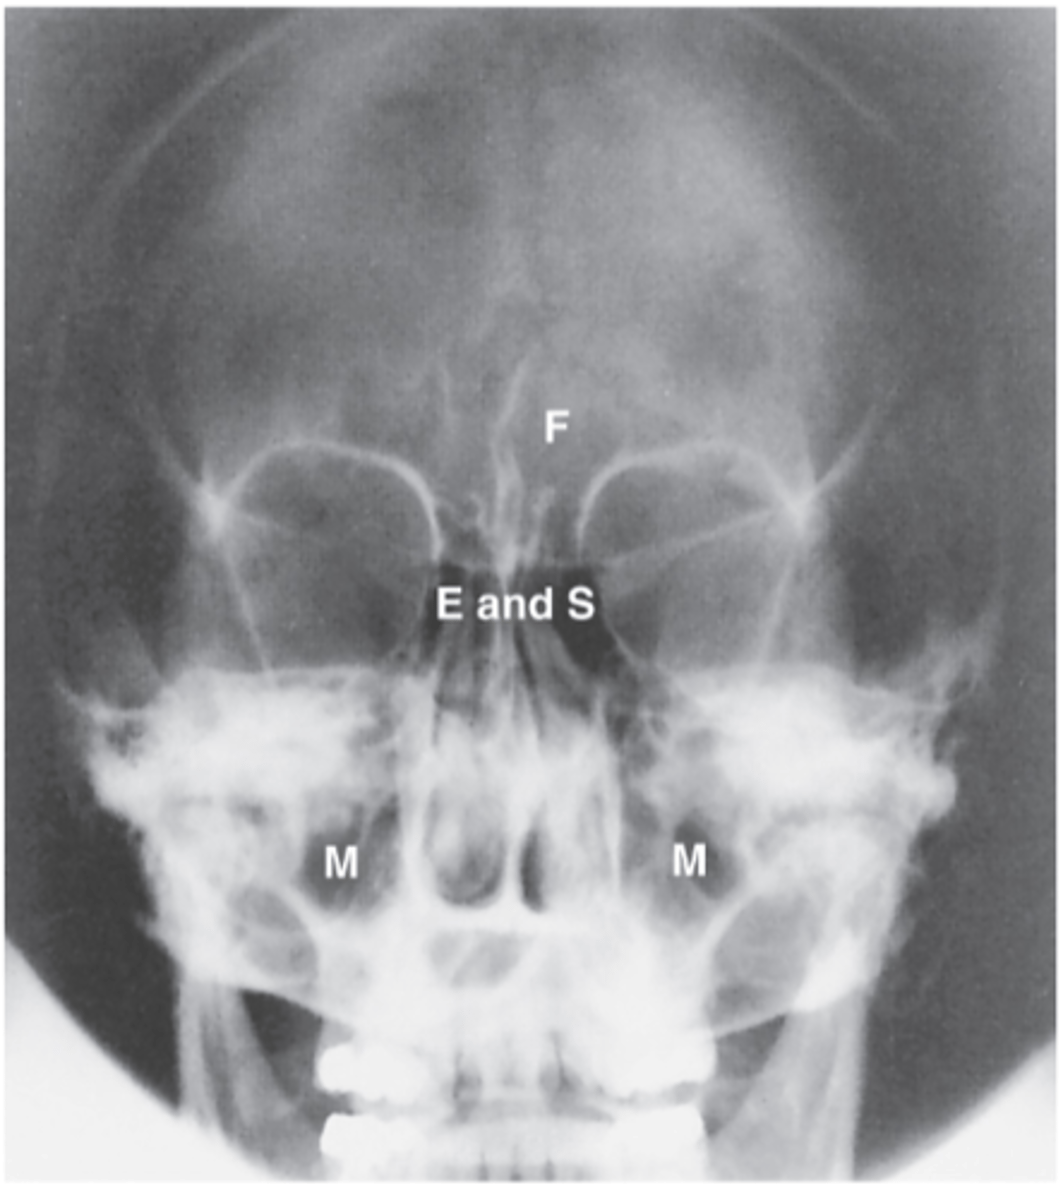

Ethmoid Sinus

E

Sphenoid sinus

S

Maxillary sinus

M

Frontal sinus

F

PA axial (Caldwell Method)

What projection is this?

CR exits the nasion & 15 degree caudal angle

What is the CR for PA axial (Caldwell Method)?

OML perpendicular to IR

What line should be perpendicular to the IR for a PA axial (Caldwell Method)?

Interpupillary line (IPL)

What line is parallel to the IR for a PA axial (Caldwell Method)?

Frontal and Ethmoid

What sinuses are clearly demonstrated on the PA axial (Caldwell Method)?

Lower 1/3 of orbits

Where are the petrous ridges located in a PA axial (Caldwell Method) radiograph?